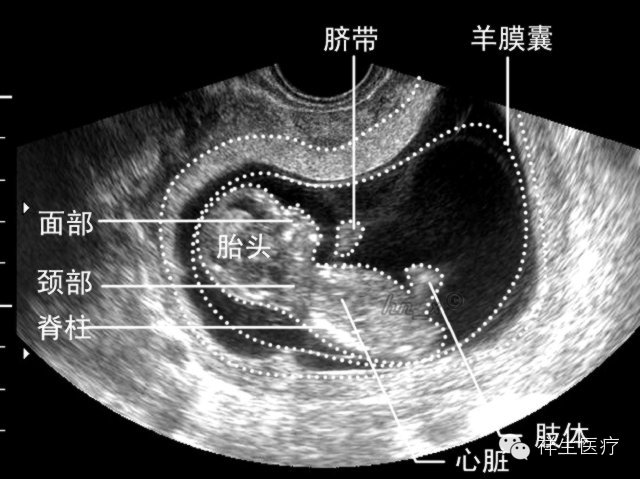

宝妈工作中总会有准妈妈们问超声仪上面看到的是宝宝哪一个部分?是头是脚?男孩还是女孩?跳动的是心脏么?

下面的这些图就会告诉你,一起看看吧!

4.孕8周:初具人形,各部分迅速发展,头颅、躯干、四肢显示越来越清楚。

5.孕9周:此时开始称为胎儿。各部分发展趋于完善,经阴道超声扫查已能观察大部分结构。

8.孕13-27周均属于中期妊娠。在此期间可以检测胎儿的生长发育情况,了解胎儿构造及羊水胎盘情况。

a.头面部

b.四肢

c.心脏